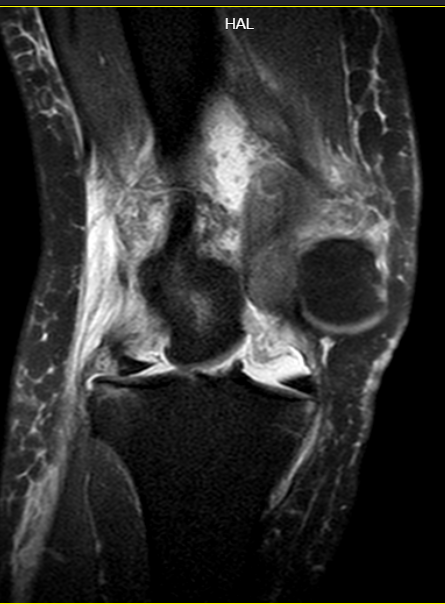

MR检查可见膝关节脱位、前后交叉韧带断裂、内侧副韧带断裂并卡关节内(导致关节无法复位)